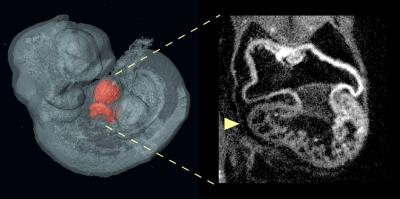

Normal heart formation depends on interactions of multiple types of cells that collaborate in precise times and places throughout development to build the heart's intricate structures. To figure out how these interactions can go awry, the Calof-Lander team studied atrial septal defects (ASDs, a common type of heart defect) in a mouse model of the developmental disorder Cornelia de Lange Syndrome (CdLS).

Employing genetically modified mouse models, the researchers used a novel technology to selectively introduce or remove Nipbl mutations in different tissues during embryonic development. Unexpectedly, they found that no Nipbl deficiency in any single tissue -- including the tissue that forms the heart itself -- could singlehandedly account for the development of atrial septal defects. Rather, the development of heart defects was determined by interactions between heart-forming tissues and the rest of the body. In fact, Nipbl deficiency in some tissues even seemed to protect against the development of atrial septal defects, in certain situations.